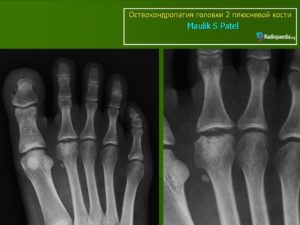

Развитие и терапия асептического некроза кости

Асептический некроз любой кости тела (например, плюсневой или ладьевидной кости) является патологическим процессом, при котором она гибнет. Некроз – это, другими словами, омертвение клеток и тканей в организме. Из-за этого прекращаются их функции, нарушается кровообращение в пострадавшей части.

Некроз может поразить область ладьевидной кости ступни и кисти, плюсневые, бедренную и полулунную кости, а также фаланги пальцев.

Диагностика и лечение проблемы

Проблемы, связанные с некрозом костей, диагностируют с помощью рентгена и МРТ, которое позволяет измерить и внутрикостное давление.